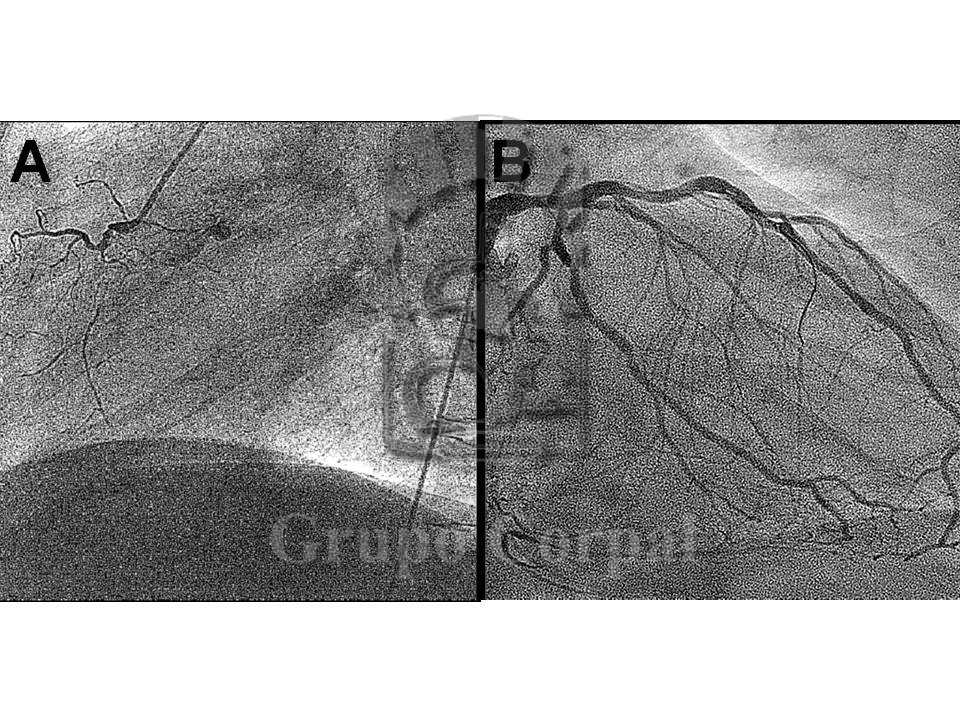

Figura 6: Esta Figura muestra comparativamente la Coronaria Derecha en proyección OAI-45 tras el procedimiento (A) y a los 3 años de seguimiento (B).